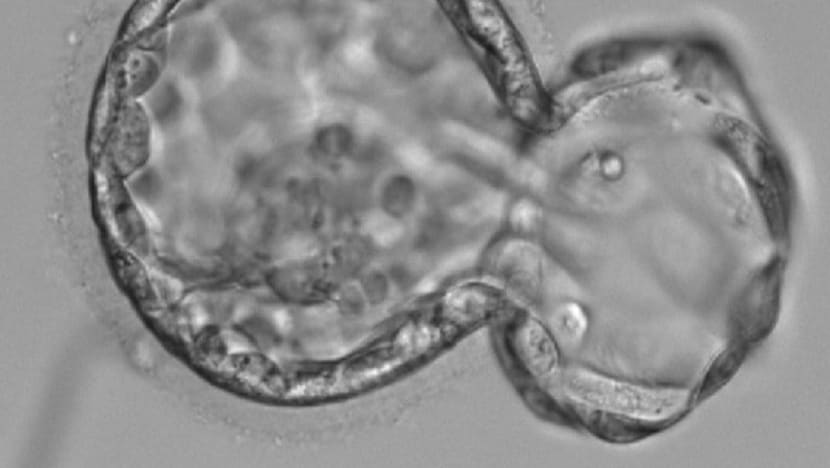

A Day 5 embryo under the microscope.